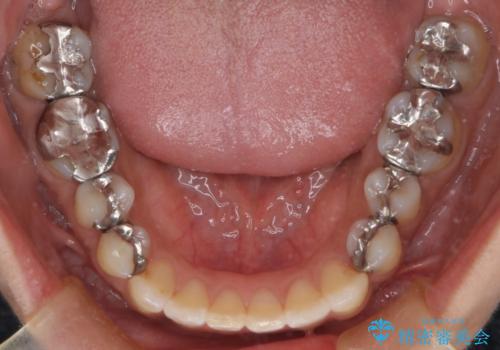

【インビザライン】前歯の凸凹をなおしたい

- 前歯の凸凹を主訴に来院されました。

インビザライン にて治療を行い、歯並びの改善を行うことができました。